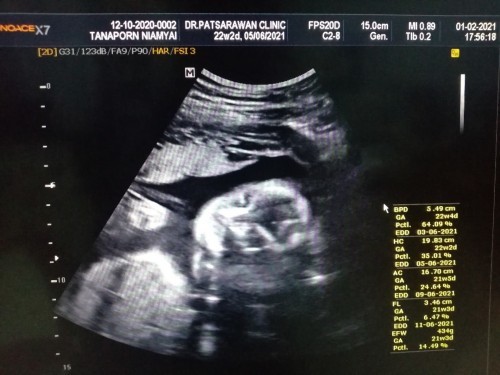

23week2day น้องเป็นผู้หญิงค่ะ กำหนดคลอด5มิ.ย64 ตัวเล็กดิ้นกันบ้างรึยังค่ะ บ้านนี้รู้สึกการดิ้นได้ชัดแล้วค่ะ ☺️☺️💓 ท้องที่2ค่ะ (คนโตเป็นผู้หญิงค่ะ) หาเพื่อนให้ตัวเล็กจ้า💕💕 #ขอบคุณสำหรับคำตอบค่ะ #ขอบคุณล่วงหน้านะคะ